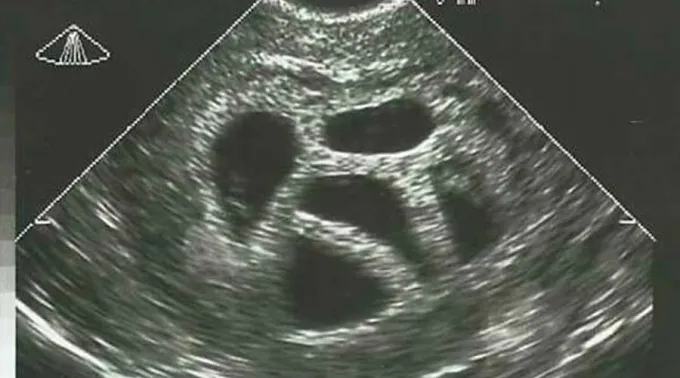

Susan compartilhou a imagem da ultrassonografia em setembro de 2015. Nela se observam cinco bolsas gestacionais, que correspondem a seus cinco filhos, atualmente com 20 anos.